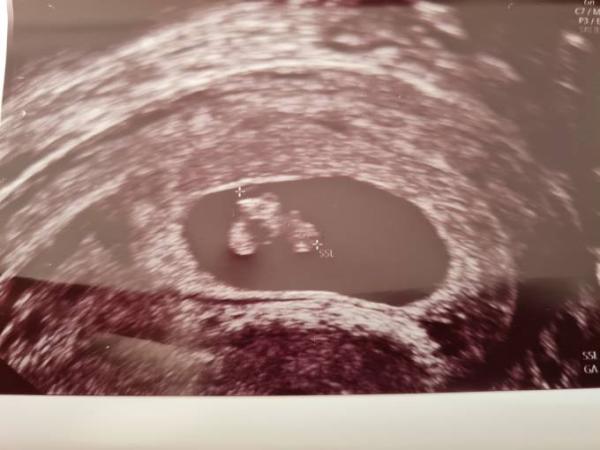

Mädchen können ja auch 3 so knubbel haben. Der Arzt wollte nichts dazu sagen erst in 3 Wochen dann.

Hier 8 ssw

Fur mich sieht das nach einen jungen aus. Erkenne einen hodensack und einen schnippi.

Für mich sieht es auch nach einem Jungen aus.

Tippe auch auf Team blau Lg

Eindeutig Junge. Weiß nicht wie man da ein Mädchen sehen kann